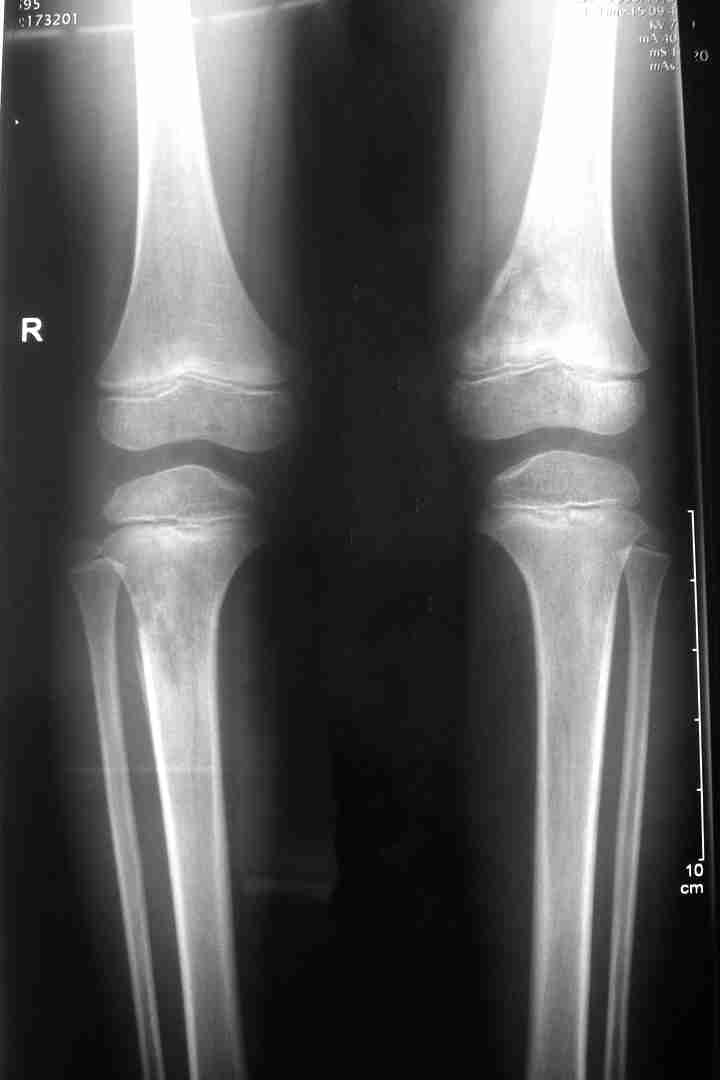

男孩5岁,下肢疼痛1年余。

多骨溶骨性破坏,累及干骺端,可见骨硬化增生,可见软组织肿块,有明显骨膜反应,患者男性,5岁,病史一年,考虑骨恶性肿瘤,成神经细胞瘤,ewing瘤,骨母细胞肉瘤及转移等可能性大,另不除外黄脂瘤